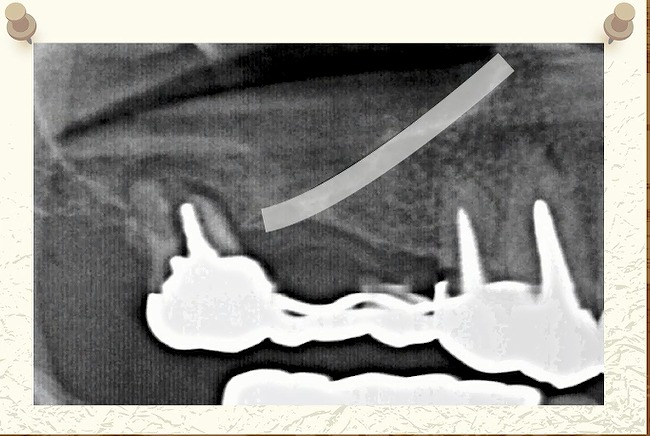

別の方のCT写真です。

歯の頭の位置で

輪切りではなく

縦に切って撮影した写真です。

ここに黒い部屋があります。

ここは鼻の部屋です。

つまり

硬いものが白くうつるわけですから

空気がある

鼻の部屋ですから

空気があるわけです。

指している

空気がないといけないところに

何かうつっていますね?

何かが鼻の中にある

というところですね。

副鼻腔

上顎洞の中の場所になりますので

副鼻腔炎

という病名がつきます。

もっと見てみると

少し歯の根っこが

鼻の部屋に入り込もうとしています。

こちらはどうでしょうか?

完全に鼻の中に

歯の根っこがめり込んでしまっています。

硬い骨があって

歯の根っこがどんどん

突き上げられていって

突き抜けている

ということが

わかります。